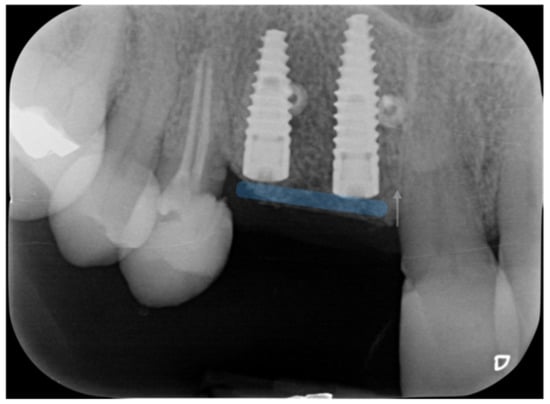

The radiographs at baseline and after completion of the prosthetic restoration also show the GTR effect of GBR in this case on the natural teeth, aside from the expected effect on bone and implants. Both bony peaks to the distal of 11 and mesial of 14 are coronal to the head of the fixture and support interdental papilla (Figure 20 and Figure 21). It is possible to appreciate in the radiographs the stability and good mineralization of the grafted area.

Figure 20.

The supra-crestal component of the bone lamina (blue) and the GTR effect near tooth 11 (white arrow).

Figure 21.

Rx of follow-up completion of restoration (left) and at 3 years after load (right).